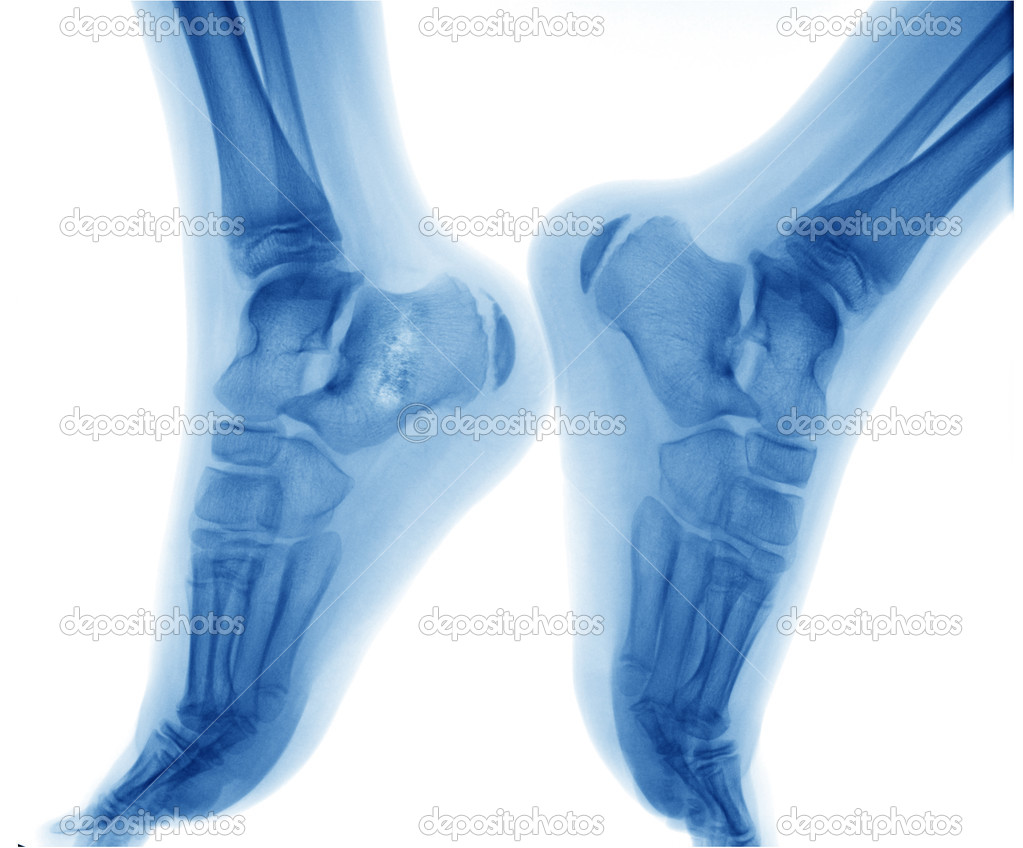

Рак кости стопы - фото и фотографии . Шаблоны . Видео рак костей . Векторы рак костей . Топовая коллекция рак костей . кт . рентген . череп человека . рак позвоночника .